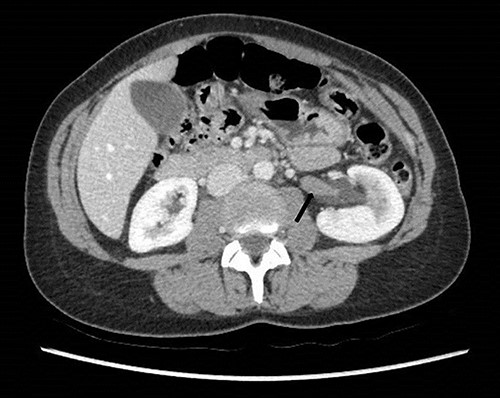

To investigate the bleeding source, she subsequently had a CT renal angiogram 3 days later that showed a narrow angle between origin of SMA and the aorta (Fig. 3) with multifocal areas of hypoattenuation throughout the left renal cortex (Fig. 4). It showed a compression ratio of 3.25 (diameter of pre-compressed vein =6.5 mm; diameter of compressed vein =2 mm) (Fig. 5).

Computed tomography angiogram on presentation showing pre-compressed LRV (right arrow); and compressed LRV (left arrow).